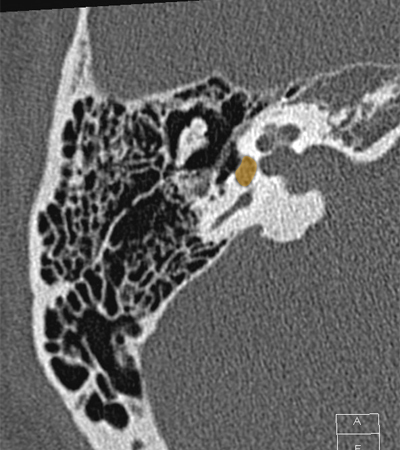

Cochlea Internal auditory canal Vestibule Posterior semicircular canal Head of malleus Body of incus Incudomallear joint